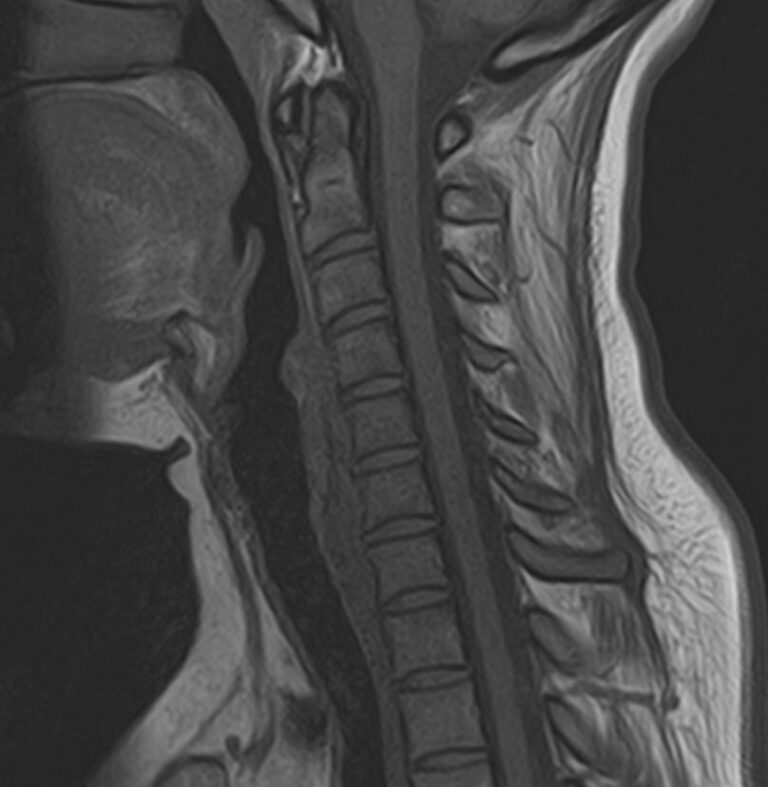

В клинике «Доступная медицина» можно пройти комплексное обследование, включающее в себя два протокола сканирования близко расположенных друг от друга анатомических областей – шейного отдела позвоночника и головного мозга. Метод комплексного обследования оценивает состояние всех структур головного мозга и самого верхнего сегмента позвоночного столба, который включает в себя 7 шейных позвонков, спинной мозг с отходящими от него нервными корешками и окружающими мягкими тканями.

Сканирование проводится на современном высокопольном магнитно-резонансном томографе закрытого типа TOSHIBA VANTAGE TITAN 1,5 Тесла. Магнитно-резонансный томограф производит послойное сканирование исследуемой зоны в разных плоскостях, затем при помощи компьютерных программ преобразует полученные данные в трехмерные изображения с высокой степенью детализации.

Что показывает МРТ головного мозга + шейного отдела позвоночника

В рамках проведения данного комплексного исследования можно выявить:

• остеохондроз, спондилоартроз, спондилез, межпозвонковые грыжи, унковертебральный артроз, сколиоз, усиленный или выпрямленный лордоз как нарушение статической функции позвоночника, травмы, аномалии позвоночника.